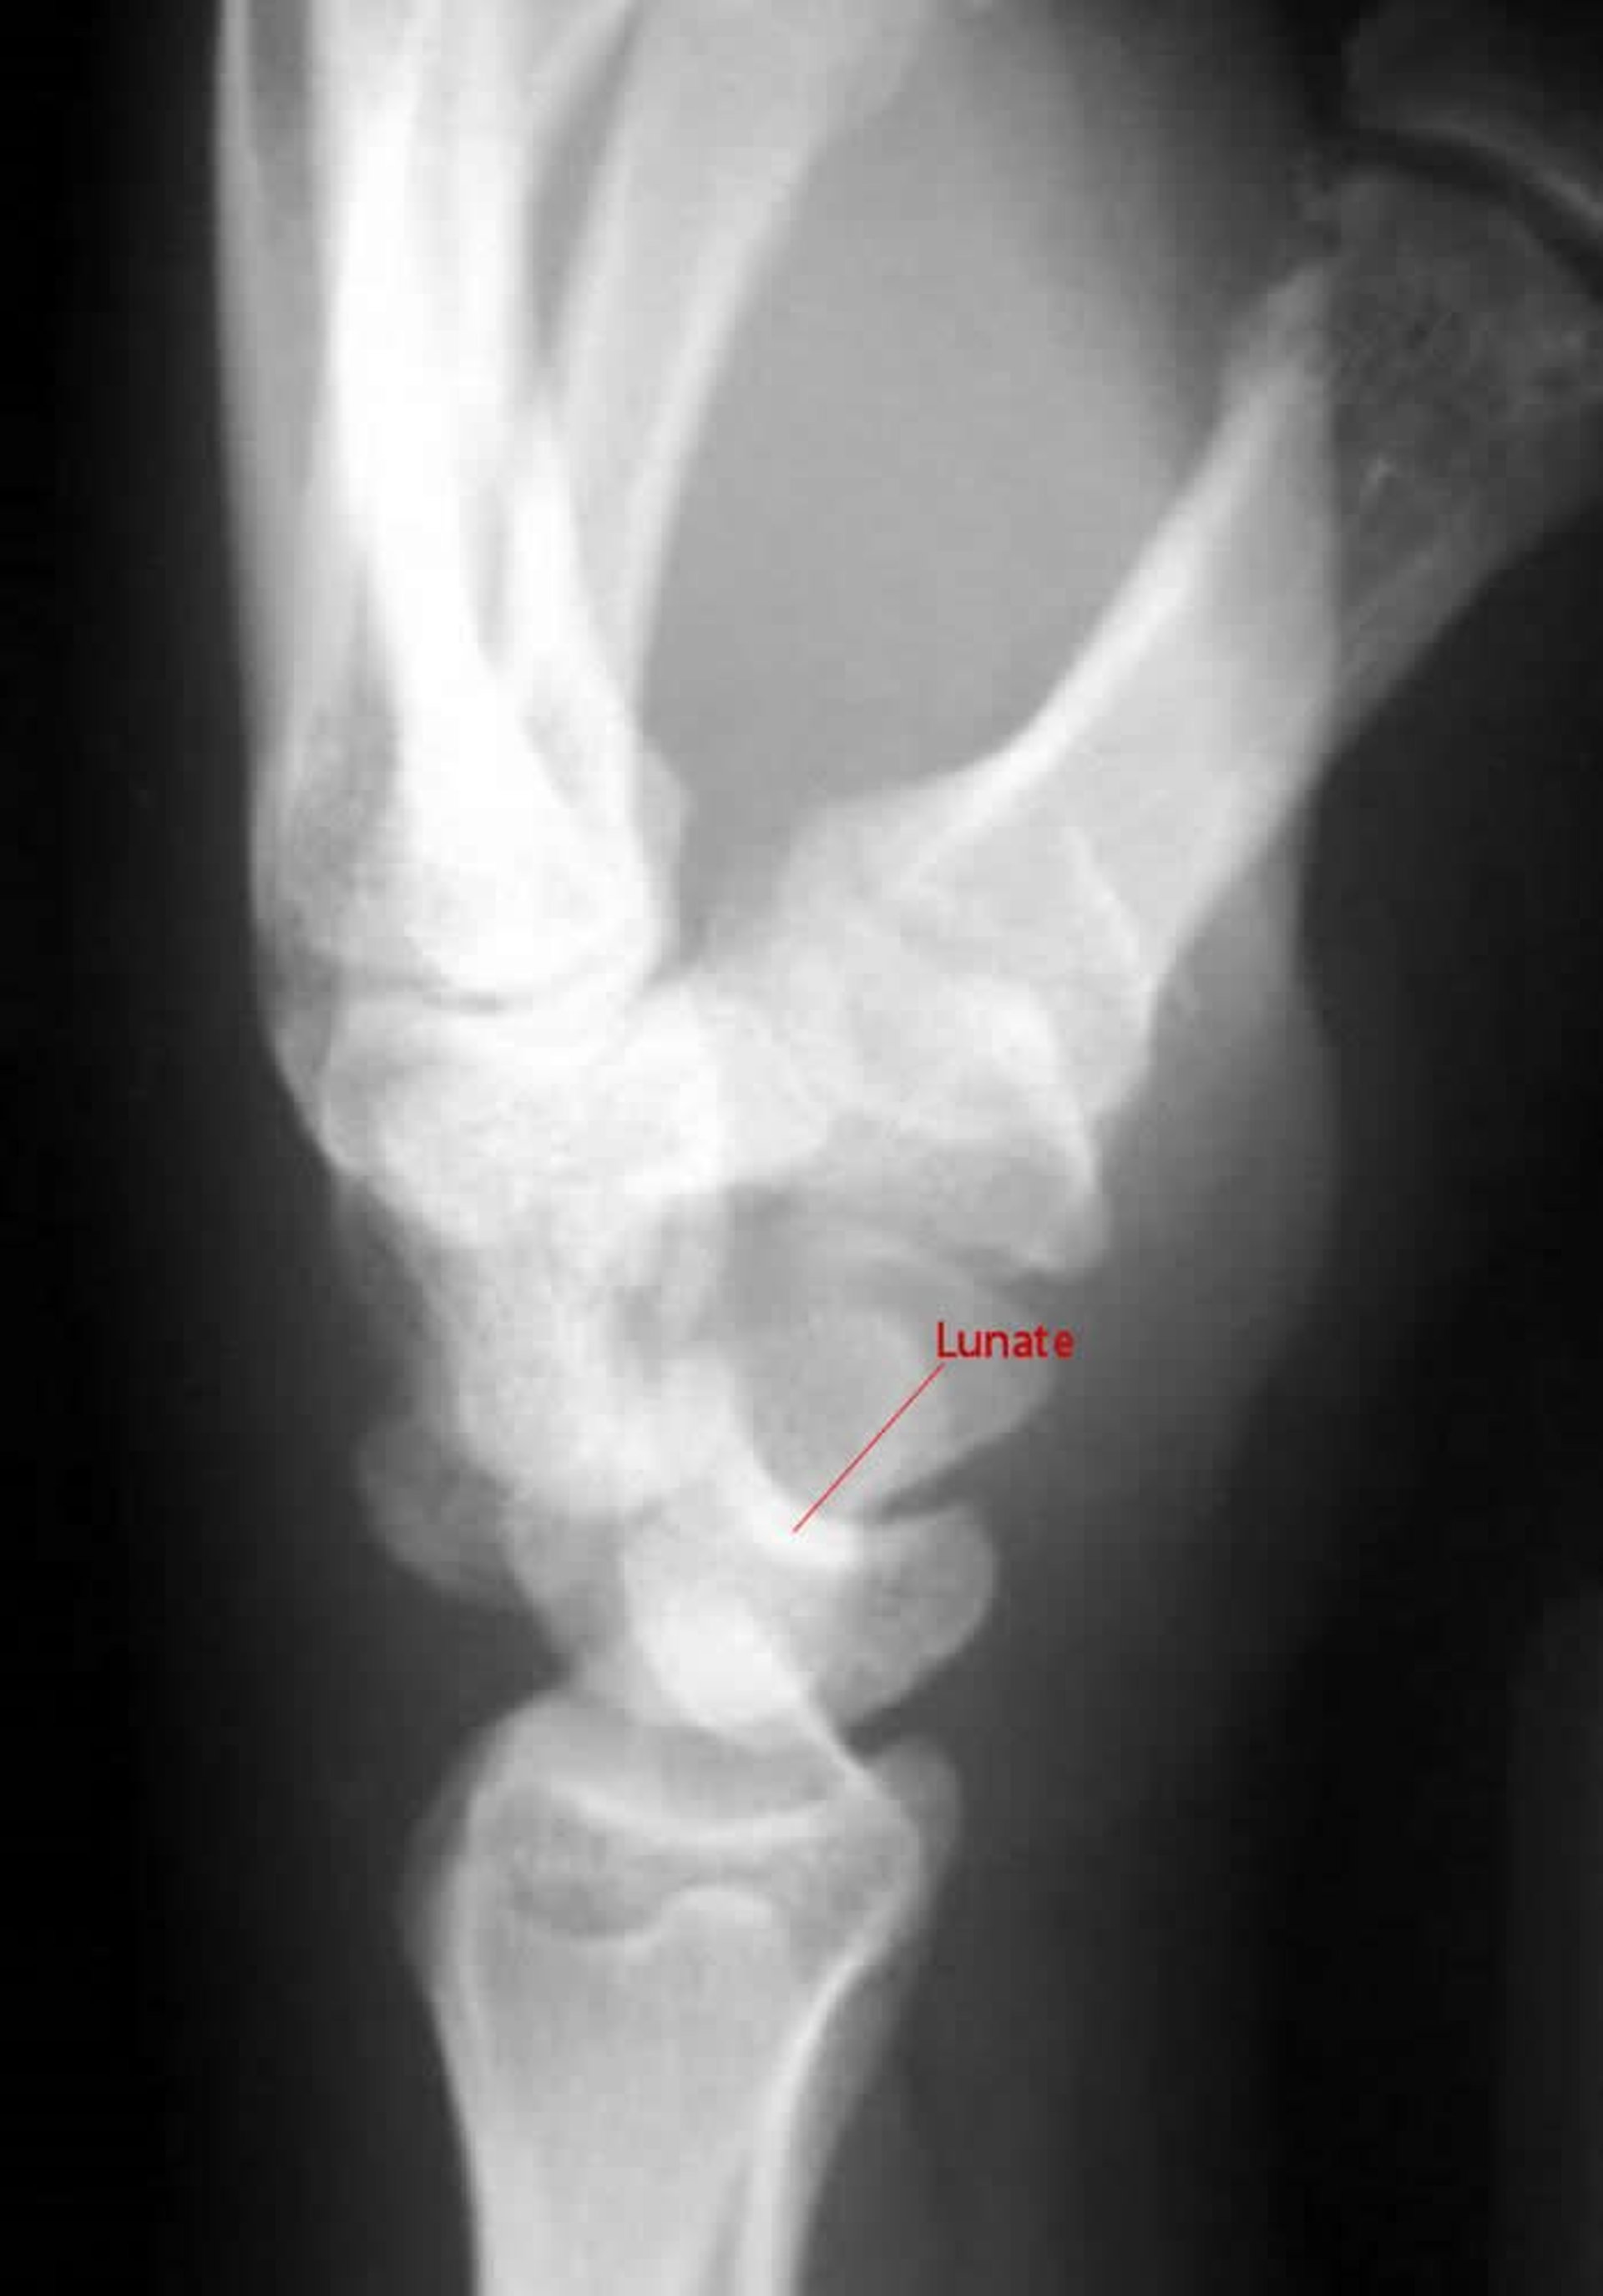

月状骨周囲の脱臼

月状骨周囲脱臼の側面像では,有頭骨は月状骨とつながっていない。

Image courtesy of Danielle Campagne, MD.